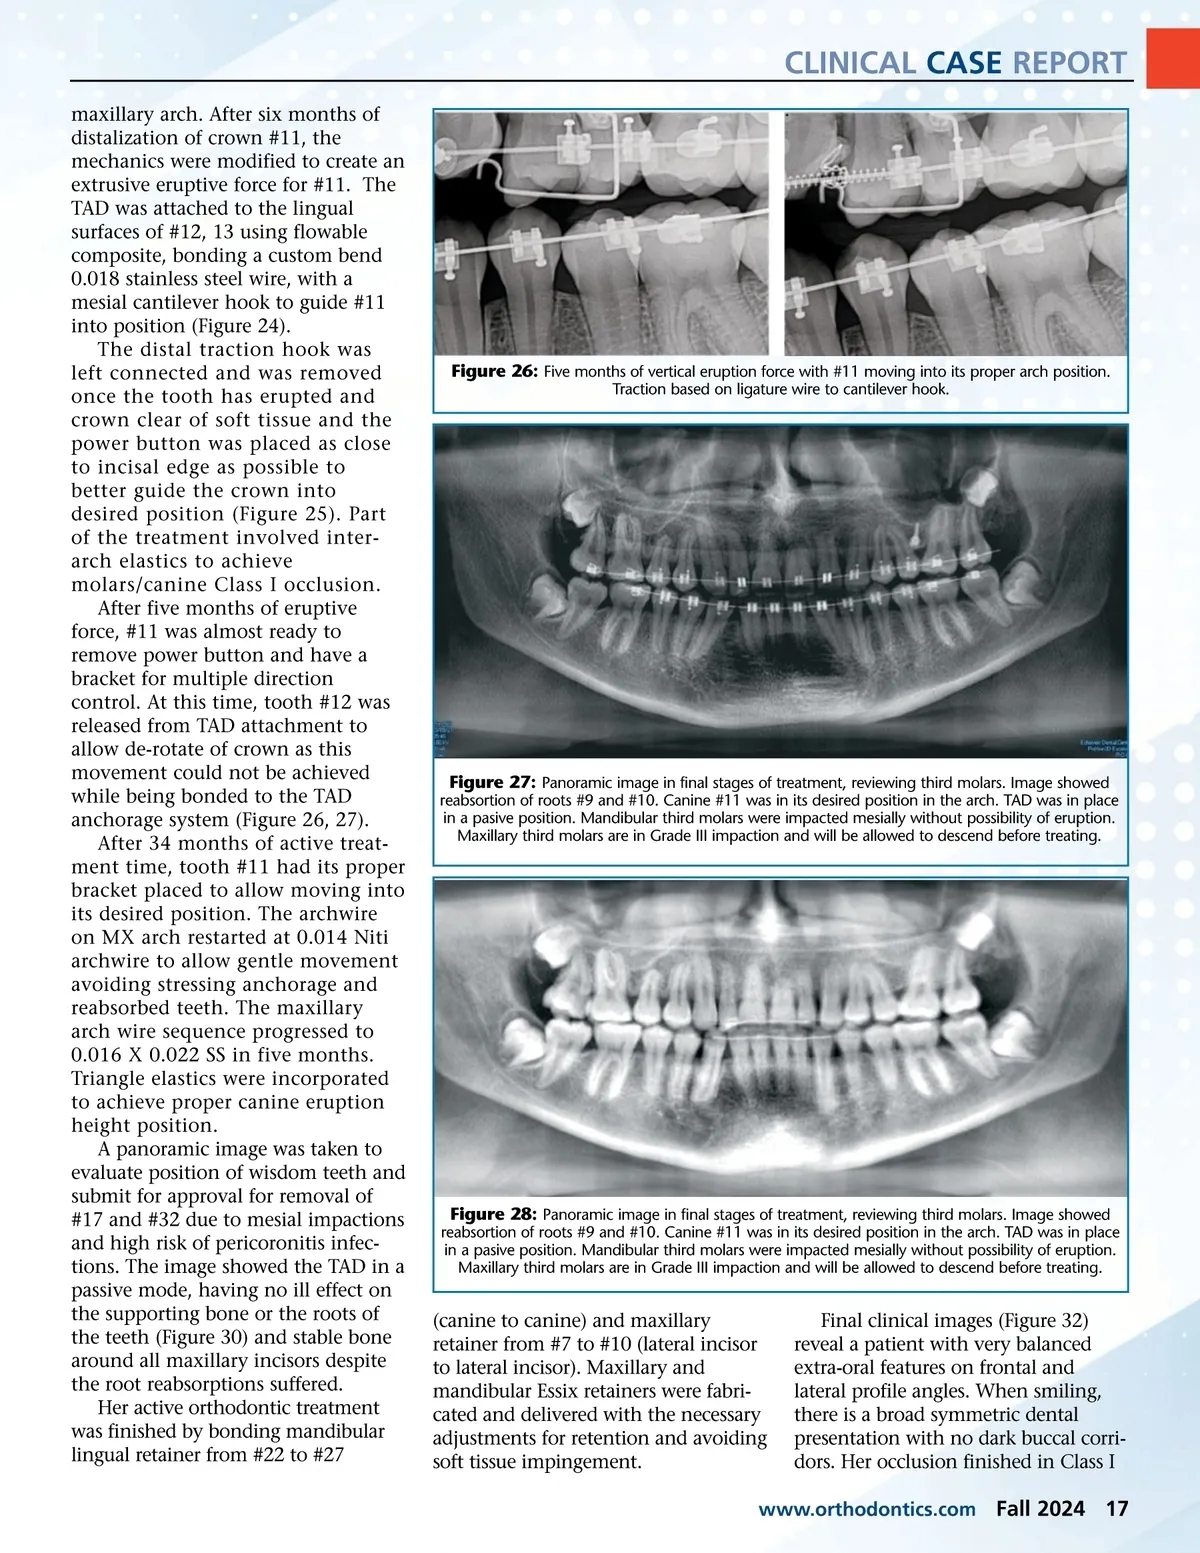

CLINICAL CASE REPORT maxillary arch. After six months of distalization of crown #11, the mechanics were modified to create an extrusive eruptive force for #11. The TAD was attached to the lingual surfaces of #12, 13 using flowable composite, bonding a custom bend 0.018 stainless steel wire, with a mesial cantilever hook to guide #11 into position (Figure 24). The distal traction hook was left connected and was removed once the tooth has erupted and crown clear of soft tissue and the power button was placed as close to incisal edge as possible to better guide the crown into desired position (Figure 25). Part of the treatment involved inter-arch elastics to achieve molars/canine Class I occlusion. After five months of eruptive force, #11 was almost ready to remove power button and have a bracket for multiple direction control. At this time, tooth #12 was released from TAD attachment to allow de-rotate of crown as this movement could not be achieved while being bonded to the TAD anchorage system (Figure 26, 27). After 34 months of active treat-ment time, tooth #11 had its proper bracket placed to allow moving into its desired position. The archwire on MX arch restarted at 0.014 Niti archwire to allow gentle movement avoiding stressing anchorage and reabsorbed teeth. The maxillary arch wire sequence progressed to 0.016 X 0.022 SS in five months. Triangle elastics were incorporated to achieve proper canine eruption height position. A panoramic image was taken to evaluate position of wisdom teeth and submit for approval for removal of #17 and #32 due to mesial impactions and high risk of pericoronitis infec-tions. The image showed the TAD in a passive mode, having no ill effect on the supporting bone or the roots of the teeth (Figure 30) and stable bone around all maxillary incisors despite the root reabsorptions suffered. Her active orthodontic treatment was finished by bonding mandibular lingual retainer from #22 to #27 Figure 26: Five months of vertical eruption force with #11 moving into its proper arch position. Traction based on ligature wire to cantilever hook. Figure 27: Panoramic image in final stages of treatment, reviewing third molars. Image showed reabsortion of roots #9 and #10. Canine #11 was in its desired position in the arch. TAD was in place in a pasive position. Mandibular third molars were impacted mesially without possibility of eruption. Maxillary third molars are in Grade III impaction and will be allowed to descend before treating. Figure 28: Panoramic image in final stages of treatment, reviewing third molars. Image showed reabsortion of roots #9 and #10. Canine #11 was in its desired position in the arch. TAD was in place in a pasive position. Mandibular third molars were impacted mesially without possibility of eruption. Maxillary third molars are in Grade III impaction and will be allowed to descend before treating. (canine to canine) and maxillary retainer from #7 to #10 (lateral incisor to lateral incisor). Maxillary and mandibular Essix retainers were fabri-cated and delivered with the necessary adjustments for retention and avoiding soft tissue impingement. Final clinical images (Figure 32) reveal a patient with very balanced extra-oral features on frontal and lateral profile angles. When smiling, there is a broad symmetric dental presentation with no dark buccal corri-dors. Her occlusion finished in Class I www.orthodontics.com Fall 2024 17